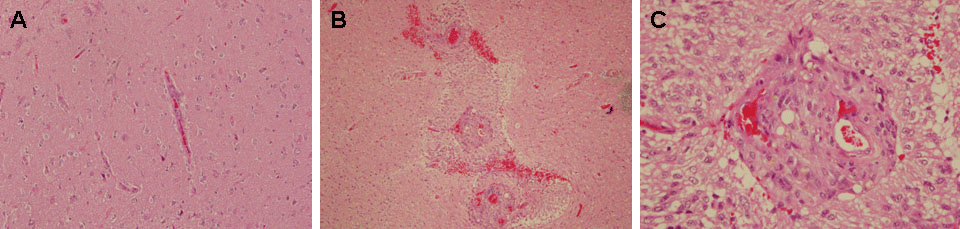

| Figure 5: Glomeruloid structures and endothelial proliferation in GBM. Comparison of normal brain at 20X (A) with GBM tissue at 10X (B), and 40X (C) demonstrates the presence of glomerular-shaped vascular walls within GBM. The leaky nature of these vessels may contribute to spread of the tumor cells. |